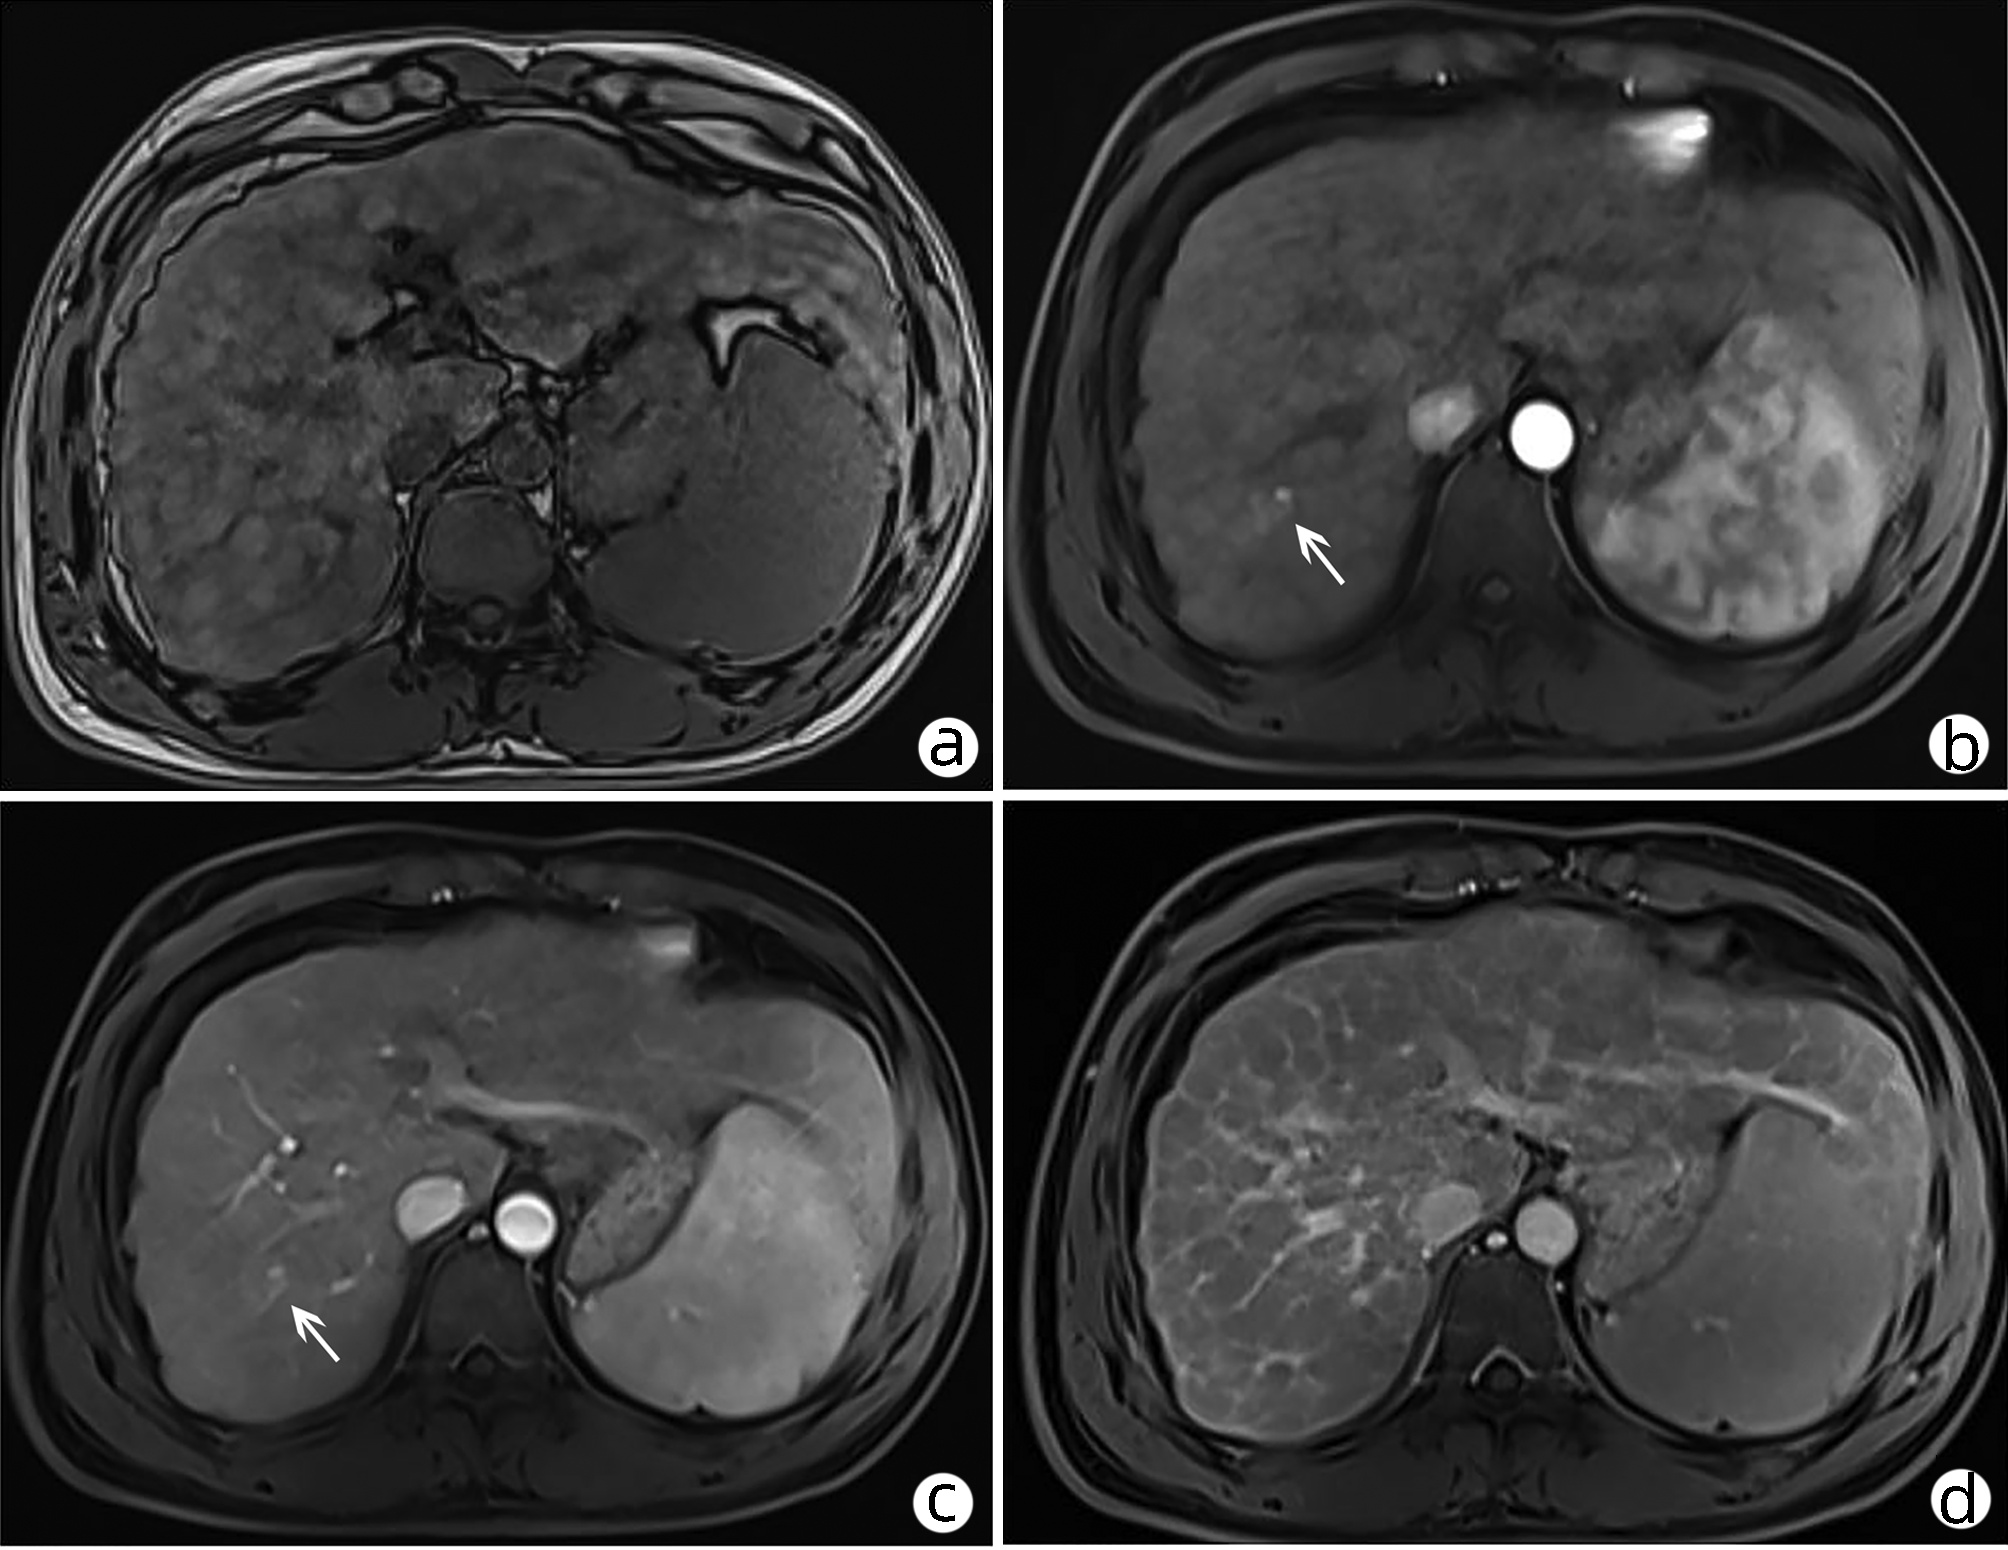

慢性乙型肝炎患者骨量减少/骨质疏松的危险因素及CT值的诊断价值

张静怡, 唐映梅, 李嘉琦, 王倩, 张宸瑞

2022, 38(5): 1041-1047. DOI: 10.3969/j.issn.1001-5256.2022.05.013

摘要(1220) HTML (508) PDF (2526KB)(83)

摘要:

目的  评价在慢性乙型肝炎患者腹部CT中通过测量胸、腰椎CT值,诊断骨量减少/骨质疏松的诊断价值。分析慢性乙型肝炎患者发生骨量减少/骨质疏松的危险因素。  方法  回顾性纳入2019年1月—2020年12月在昆明医科大学第二附属医院就诊的慢性乙型肝炎患者112例,所有患者均完善了腹部CT检查,部分患者完善了双能X线骨密度测定(DXA)。测量T12椎体至L3椎体的CT值,分析每一椎体CT值与DXA检查基于L1~L4椎体测得的T-score值相比诊断骨量减少/骨质疏松的诊断价值。以椎体CT值为诊断标准,将纳入的慢性乙型肝炎患者分为骨量减少/骨质疏松组(n=55)与骨量正常组(n=57),对比两组患者临床特征、生化指标,分析慢性乙型肝炎患者发生骨量减少/骨质疏松的危险因素。符合正态分布的计量资料两组间比较采用t检验;非正态分布的计量资料两组间比较采用Mann-Whitney U检验。计数资料组间比较采用χ2检验、Fisher确切检验、Bonferroni校正检验。相关性采用Pearson相关分析。多因素分析采用二元logistic回归分析。根据受试者工作特征曲线(ROC曲线)评估T12~L3椎体CT值诊断慢性乙型肝炎患者合并骨量减少/骨质疏松的诊断价值。一致性检验采用Kappa检验。  结果  分析46例在同次住院中完善了腹部CT和DXA检查患者的T12~L3椎体CT值,均分别与DXA检查结果中基于L1~L4椎体计算的T-score值有显著正相关性(rT12=0.694,rL1=0.661,rL2=0.781,rL3=0.685,P值均<0.001);经ROC曲线分析,L2椎体CT值ROC曲线下面积最大(0.863),诊断骨量减少/骨质疏松具有较好准确性,与DXA检查结果具有较好一致性(K=0.648,P<0.001)。分析112例慢性乙型肝炎患者临床特征、生化指标,提示高龄(比值比为1.108,95%CI:1.026~1.196,P=0.009)、合并肌少症(比值比为2.788,95%CI:1.009~7.707,P=0.048) 是骨量减少/骨质疏松发生的危险因素。  结论  慢性乙型肝炎患者常需定期复查腹部CT评估肝脏疾病进展情况,通过测量患者腹部CT图像中L2椎体CT值、L3椎体层面骨骼肌面积筛查是否存在骨量减少/骨质疏松、肌少症,及时干预,提高患者的预后、生活质量,具有较高临床意义。